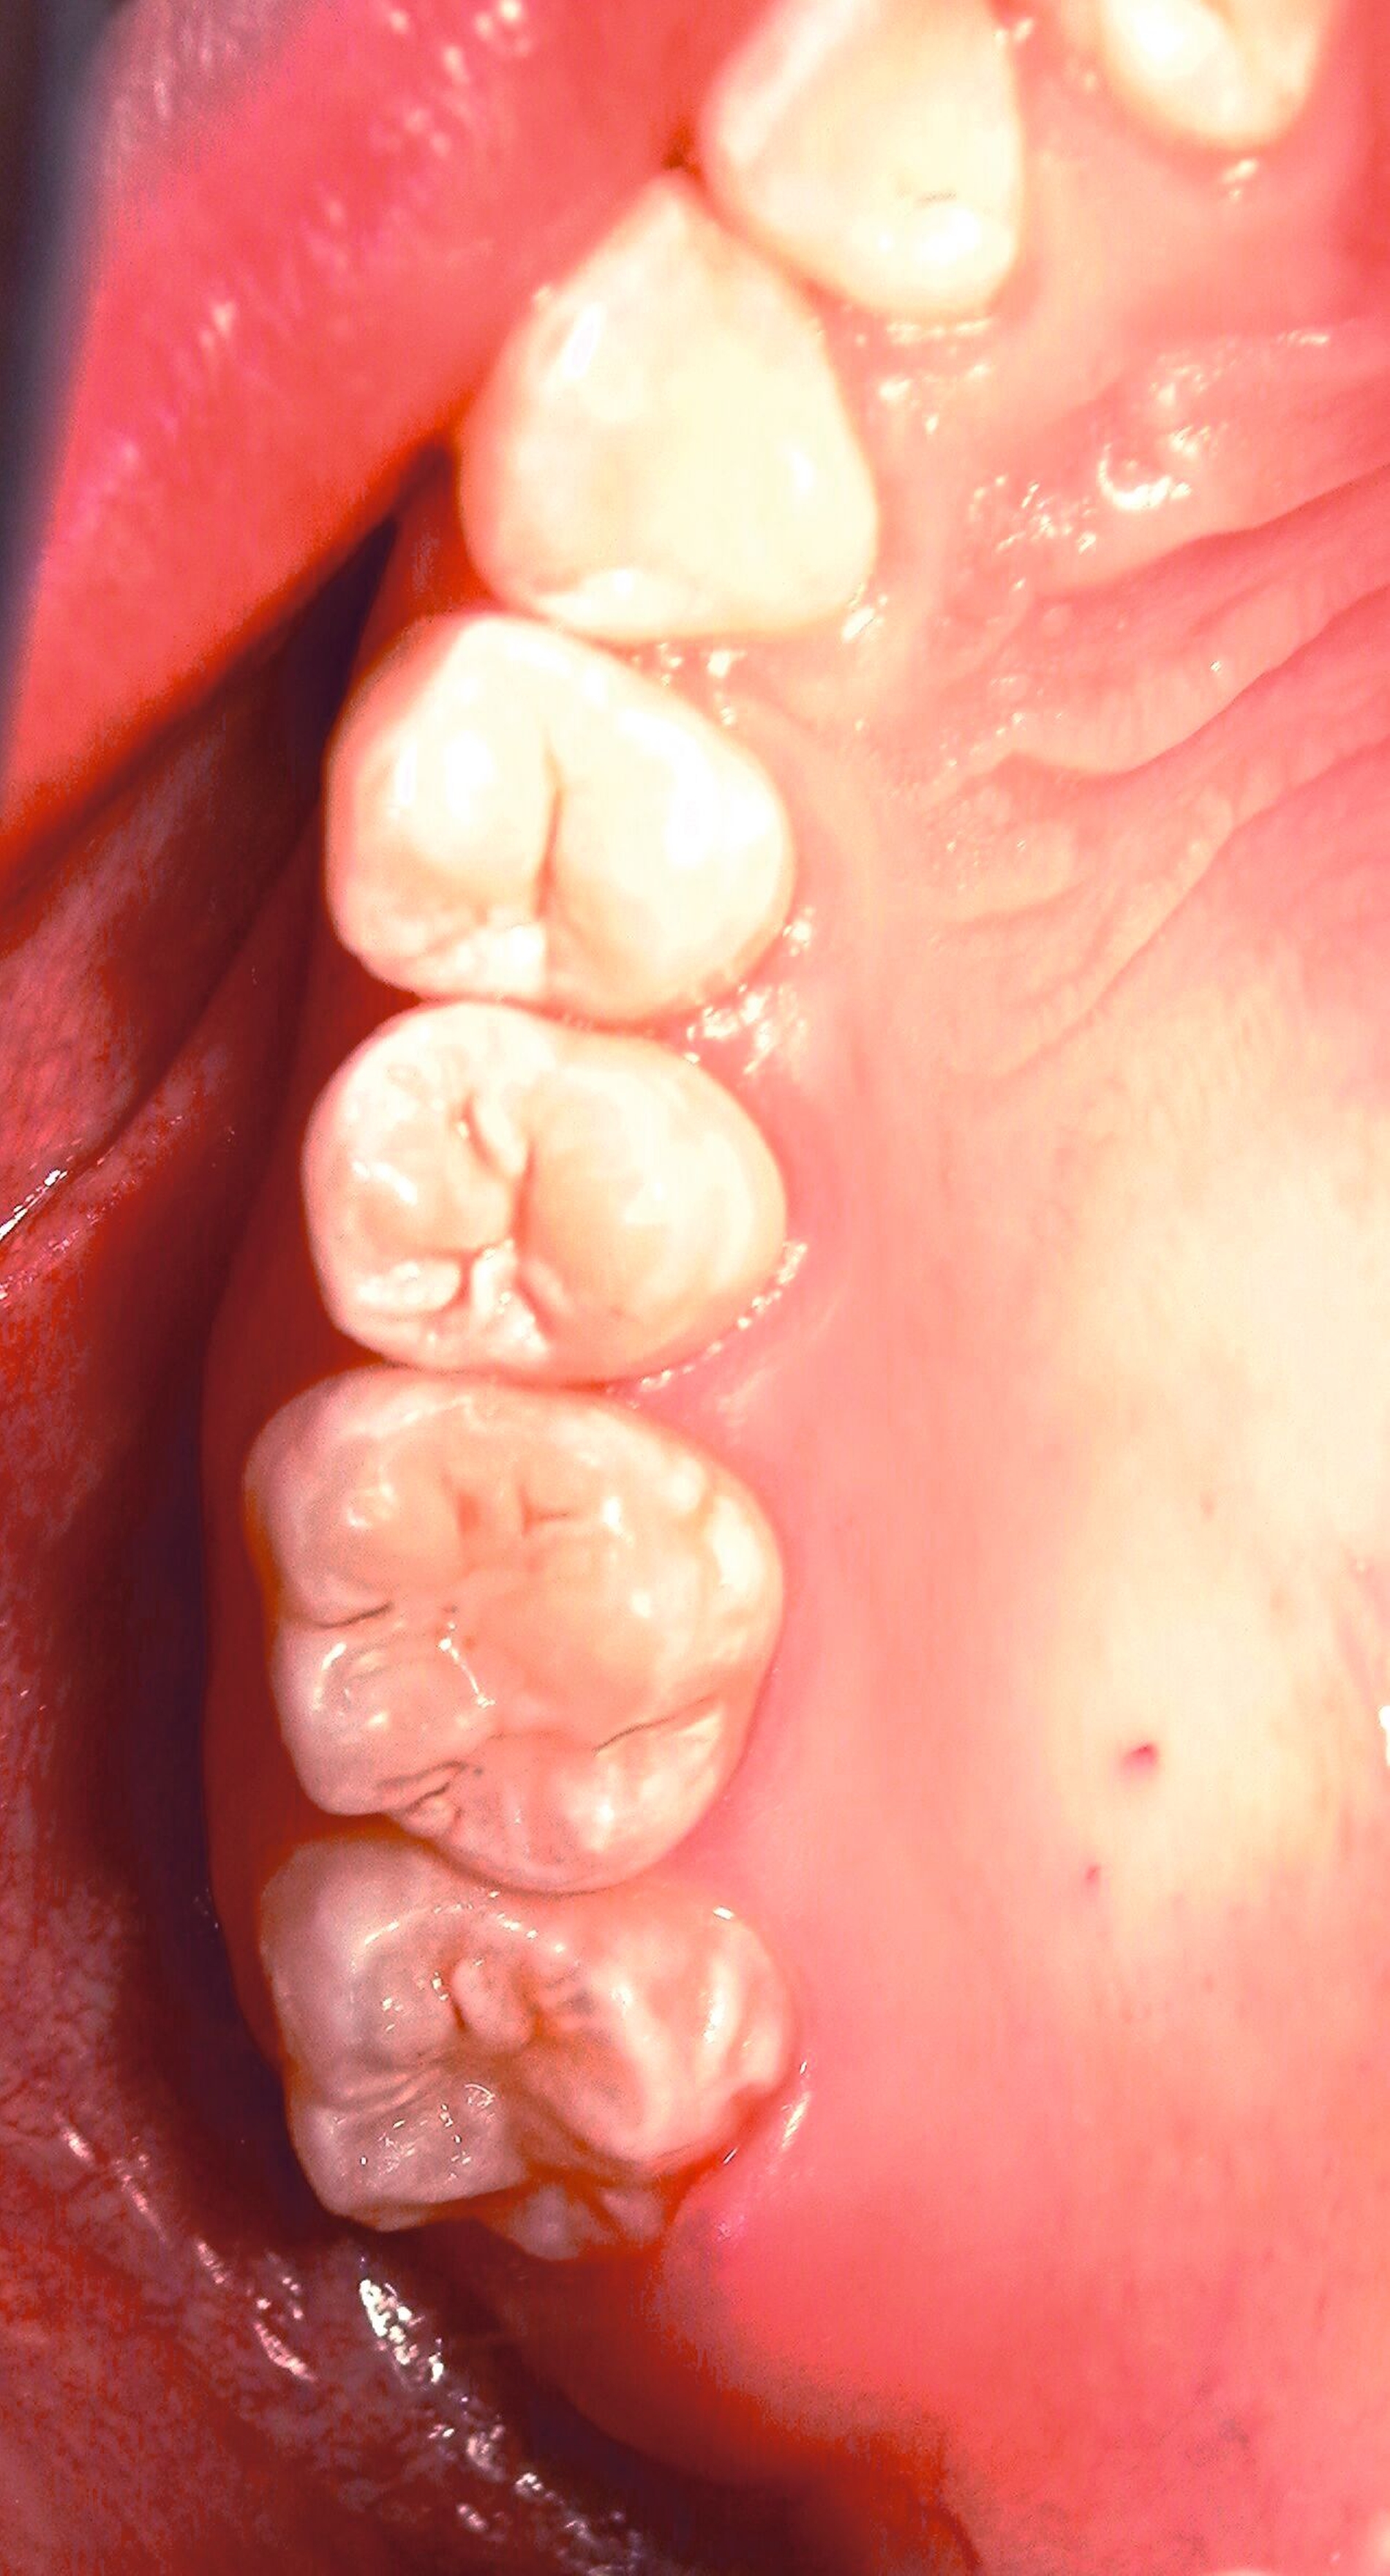

Sowohl im Unter- als auch im Oberkiefer wird letztlich ein primärer, adaptierender Wundverschluss durchgeführt (Abbildungen 12 und 15) mit Einzelknopfnähten entlang der Schnittführung, mit Beginn an der mesialen Entlastung. Dabei wird das Nahtmaterial in monofil und polyfil, synthetisch und natürlich, resorbierbar und nicht-resorbierbar, beschichtet und unbeschichtet eingeteilt [Faris et al., 2022; Minozzi et al., 2009].

Zum Wundverschluss eignen sich nicht resorbierbare, monofile, synthetische Nähte aus Polyglycolid sowie Polypropylen, da diese weniger Gewebereaktionen und mikrobielle Akkumulation hervorrufen und sich positiv auf die Wundheilung auswirken. Negativ wirken sich Seide-Fäden aus, da sie Entzündungsreaktionen auslösen und eine Affinität zur mikrobiellen Adhärenz zeigen [Dragovic et al., 2020; Faris et al., 2022].